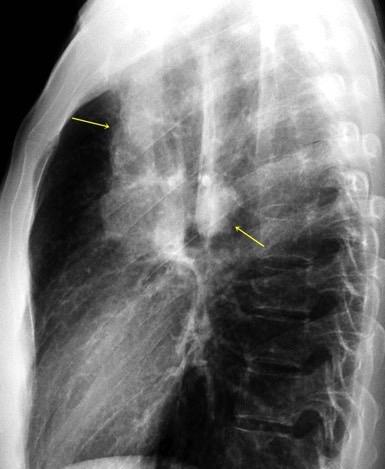

Visible en el adulto normal por interfase de la pared externa de la aorta con el aire del LII.

Causas de alteración

Normal

Patología aórtica Disección/ Aneurisma Úlcera ateroesclerótica

Adenopatías/ Ca. de Pulmón Hematoma Patología del LII

30 años

Borramiento de la banda PARA-aórtica por AdenoCa. de LII, no visible en 2005

Colapso de LII. TC: secreciones bronquiales.

Endoscopia tapón mucopurulento extraído

Borramiento parcial por Ca. epidermoide.